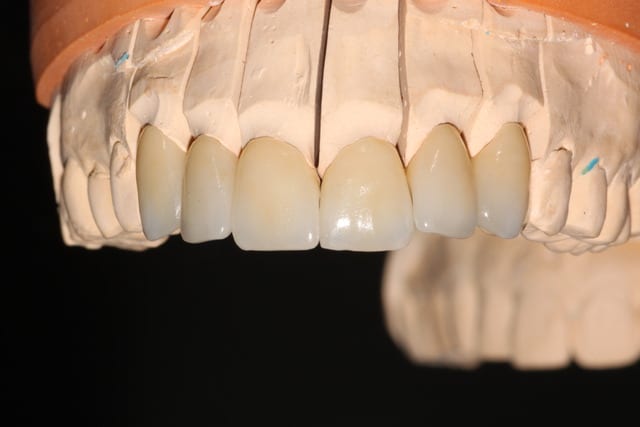

Allez, posé y'a 15 minutes. Collage multilink.

Img 2978 tqx1pw - Eugenol

Img 2984 bxc0kj - Eugenol

Img 2973 ewwctg - Eugenol

Belles préparations , attention par contre à ne pas trop " creuser" le congé (voir 22), ce qui entraîne une limite un peu pointue et fragilise la céramique.

> Belles préparations , attention par contre à ne pas trop " creuser" le congé

> (voir 22), ce qui entraîne une limite un peu pointue et fragilise la céramique.

-preps un peu agressives, j'étais du même avis en voyant le modèle, c'est pour ça que je les ai postées: comme ça c'est confirmé. Je vais avoir la main un peu plus légère sur les prochaines.

-par contre pour le congé 22 23 un peu creusé, d'anciennes CCM étaient présentes, je pense donc que c'était déjà le cas sur les preps antérieures.

-A noter, ça se voit mal sur les photos, que 11 12 13 sont des couronnes 3/4, la limite palatine se situe 3mm au-dessus de la gencive.